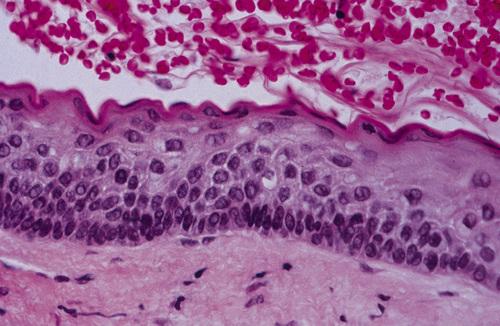

Histopathologic Features

- loosely arranged fibrous connective tissue wall

- islands or cords of odontogenic epithelial rests

- two to four layers of flattened nonkeratinizing cells

- focal areas of mucous cells in epithelial lining

This noninflamed cyst shows a thin, nonkeratinized epithelial lining and a loosely arranged fibrous connective tissue wall.

dentigerous cyst, noninflamed

This inflamed cyst shows a thick epithelial lining with hyperplastic rete ridges and diffuse chronic inflammatory infiltrate.

dentigerous cyst, inflammed

This cyst shows scattered mucous cells within the thin epithelial nonkeratinized epithelial lining.

dentigerous cyst